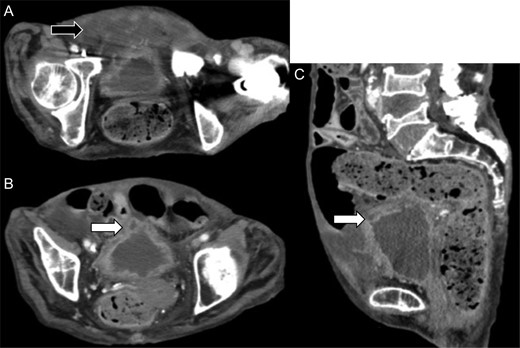

We reviewed the abdominal CT on admission, which revealed a deficit in the urinary bladder wall, with fluid collection around it (Fig. 3). The perforation of the urinary bladder was present on admission, and that of the peritoneum occurred on the following day. Previous magnetic resonance imaging revealed no diverticulum of the urinary bladder or any organic failure.

Review of the enhanced abdominal computed tomography on admission after the operation revealed (A) fluid collection in the posterior space of the urinary bladder (black arrow) and (B and C) deficit in the urinary bladder wall and suspected perforation (white arrow).